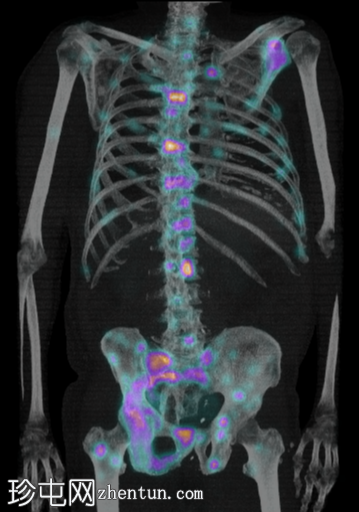

4.jpg

后位

脊柱、肋骨、骨盆、颅骨、肩胛骨、胸骨、左侧肱骨和双侧股骨干可见多处放射性示踪剂摄取异常增高,与SPECT-CT扫描图像上显示的硬化病灶相对应。双肾未见放射性示踪剂活性。

骨骼内多处局灶性放射性示踪剂摄取增高,符合骨转移;肾脏内无放射性示踪剂活性,与超扫描结果一致。